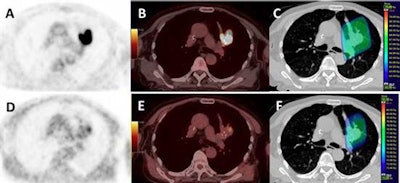

Images from a patient with an upper left lung NSCLC. (A) FDG; (B) FDG-PET/CT; (C) planning radiotherapy based on FDG (66 Gy) with BTVm (gross tumor volume), clinical target volume, and planning target volume; (D) FMISO-PET; (E) FMISO-PET/CT; and (F) boost based on the FMISO-PET (76 Gy) with BTVh (biological hypoxic target volume) and planning target volume boost. Images courtesy of Vera et al and JNM."Our approach results in a response rate of 40% or more with acceptable toxicity," concluded the group led by Dr. Pierre Vera, PhD, of the Henri Becquerel Cancer Center and Rouen University Hospital. "F-18 FMISO uptake in NSCLC patients is strongly associated with poor prognosis features that could not be reversed by radiotherapy doses up to 86 Gy."